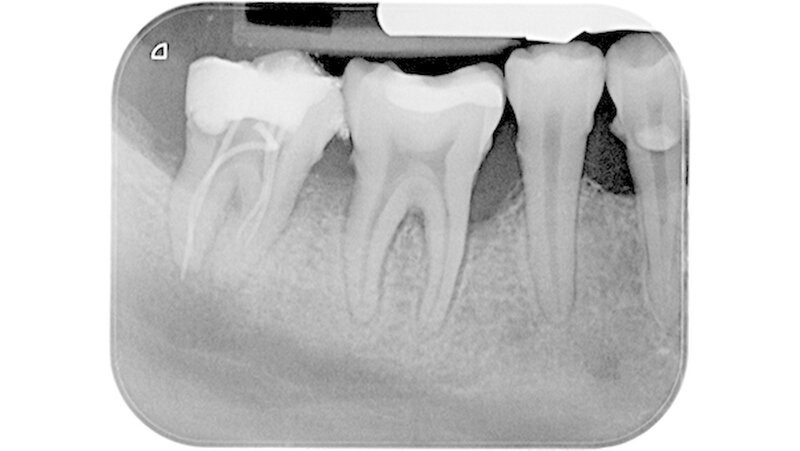

Der Zahn 47 stellte sich parodontal geschädigt und 1-gradig gelockert dar. Das Orthopantomogramm (OPTG) und der anschließend angefertigte Zahnfilm (Abbildungen 2 und 3) zeigten am Zahn 47 apikal weit überextrudiertes Wurzelfüllmaterial. Die Patientin wurde aufgrund der klinischen und der röntgenologischen Befunde sofort an die Klinik und Poliklinik für Mund-, Kiefer- und Gesichtschirurgie überwiesen.